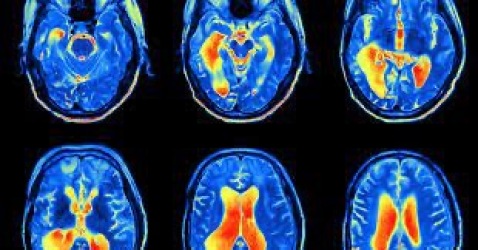

در تصویربرداری پلانار، دوربین گاما ثابت می ماند. تصاویر به دست آمده دو بعدی (2 بعدی) هستند. توموگرافی کامپیوتری با انتشار تک فوتون یا SPECT، "برش های" محوری از اندام مورد نظر را تولید می کند زیرا دوربین گاما به دور بیمار می چرخد. این برش ها مشابه تصاویری هستند که توسط سی تی اسکن انجام می شود. در موارد خاص، مانند اسکن PET، تصاویر سه بعدی (3 بعدی) را می توان با استفاده از داده های بیمار بدست آورد.

• اسکن مغز. برای بررسی مشکلات درون مغز و/یا در گردش خون به مغز استفاده می شوند.